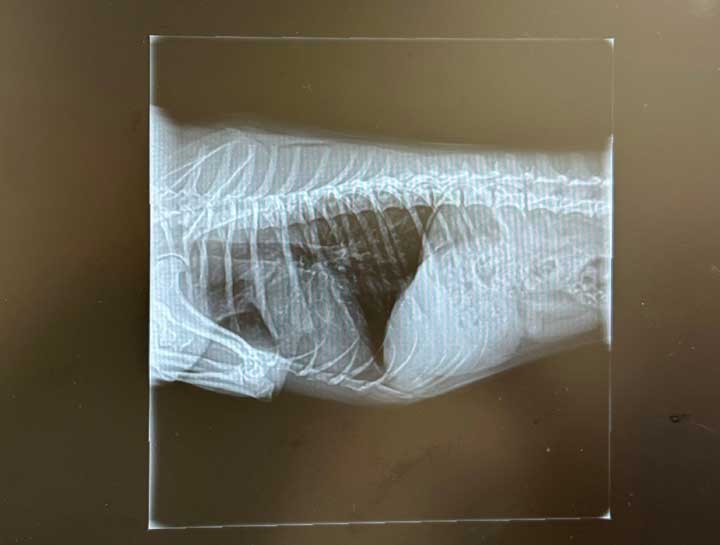

Pet Digital Radiology

Digital x-rays assist in diagnosing illness & injury.